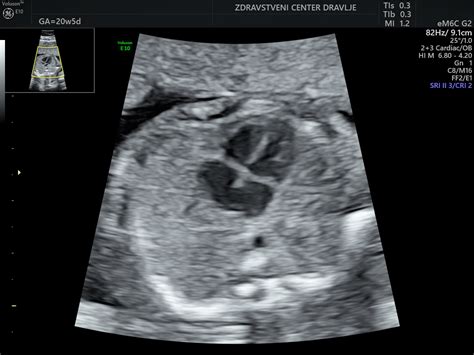

Nuhalna svetlina (NS) je, kot že omenjeno, majhna količina tekočine, ki se nabere pod kožo na vratu ploda v zgodnji nosečnosti. Povečana količina te tekočine je lahko povezana z večjim tveganjem za kromosomske nepravilnosti. Ultrazvočni pregled za merjenje nuhalne svetline vključuje natančno merjenje debeline te plasti tekočine, skupaj z drugimi parametri, kot sta dolžina plodove glave do trtice (CRL) in srčni utrip ploda. Ti podatki, skupaj z nekaterimi materinskimi dejavniki (kot so starost matere in rezultati biokemičnega testa v krvi), omogočajo izračun verjetnosti za prisotnost določenih kromosomskih nepravilnosti. V primeru visoke verjetnosti se nosečnici lahko ponudijo dodatne, bolj invazivne diagnostične metode, kot sta amniocenteza ali biopsija horionskih resic, ki lahko zanesljivo potrdijo ali izključijo prisotnost kromosomskih nepravilnosti.

Vendar pa je pomembno poudariti, da merjenje nuhalne svetline ni diagnostični test, temveč presejalni. To pomeni, da ne more z gotovostjo potrditi ali izključiti kromosomske nepravilnosti, ampak le oceni tveganje. Zato je ključnega pomena, da je pregled opravljen s strani usposobljenega strokovnjaka, ki uporablja najsodobnejšo opremo in natančno interpretira rezultate.